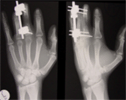

Lengthening proximal phalanx of middlefinger done using unilteral fixator at stages

2nd surgery to lengthen index and ring fingers